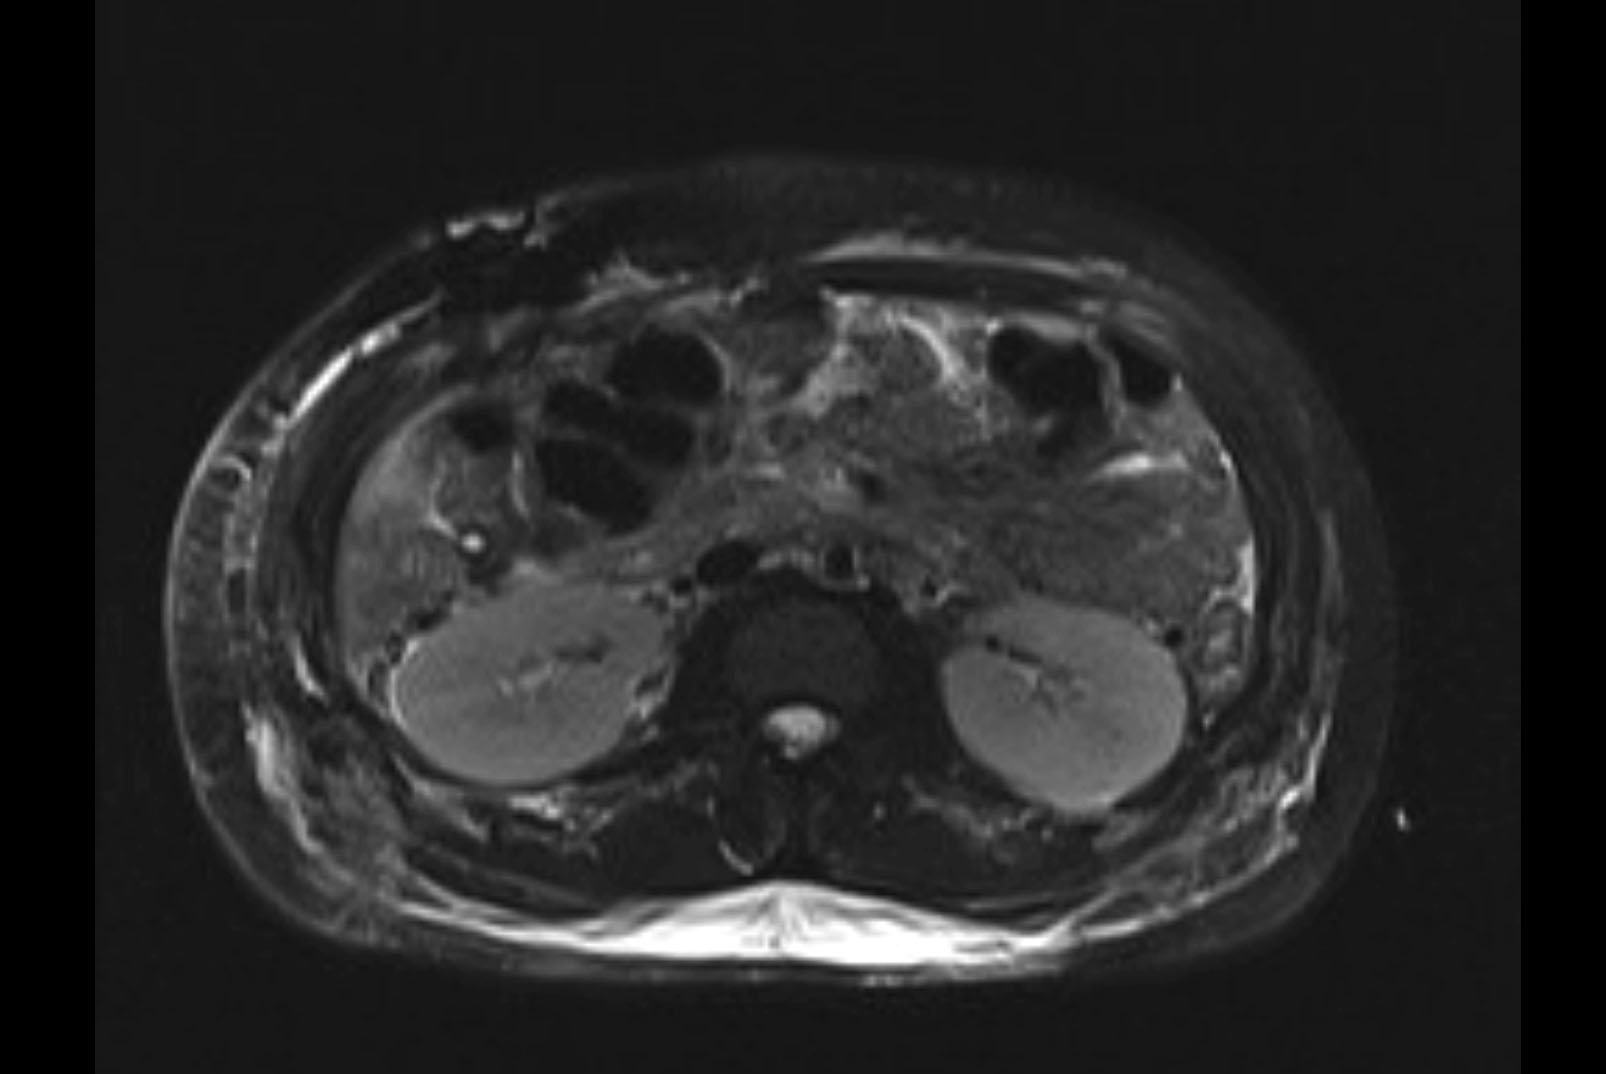

Imaging Analysis

Look through the patient's CT scan to identify any areas of concern for the necessary procedure.

MRI T2